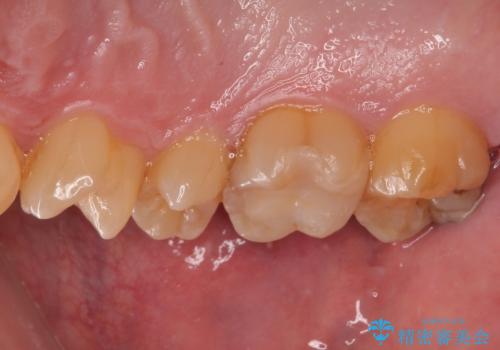

拡大鏡視野下でセラミックインレーに適した形に整えました。

歯と歯茎の間に圧排糸と言われる糸を入れてシリコーン印象材にて精密な型どりをしました。

セラミックインレーの装着時には、唾液の侵入を防ぐために、ラバーダム防湿を行いました。